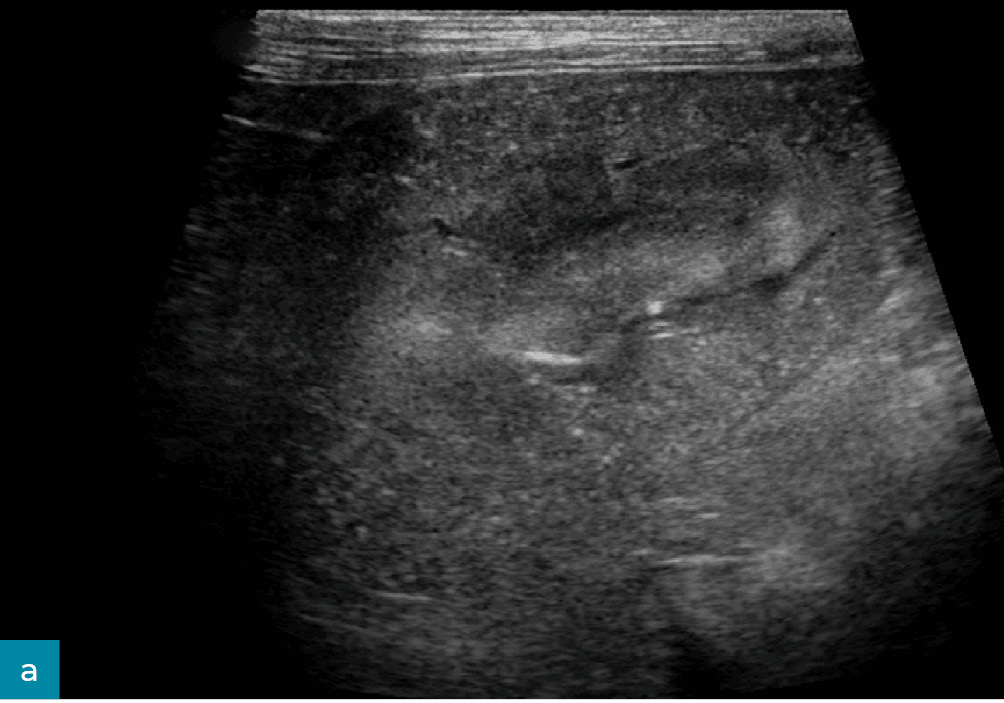

Mineralizacja

Dystroficzne odkładanie się substancji mineralnych w nefronach i śródmiąższu nerki może występować wtórnie do jej uszkodzenia i bywa trudne do odróżnienia od zwłóknienia nerek. Korelacja histologiczna jest ograniczona, przypuszcza się jednak, że mineralizacje (ryc. 11) najczęściej odpowiadają punktowym i/lub liniowym, hiperechogenicznym ogniskom w korze nerkowej, które są zazwyczaj zbyt małe, by powodować dystalny cień akustyczny.8 Hiperechogeniczne pasma w rdzeniu nerek, również uważane za przejaw mineralizacji i/lub zwłóknienia, obserwuje się w bardziej postępującej chorobie nerek.3 Tzw. objaw rąbka rdzeniowego, choć występuje zarówno u psów z przewlekłą niewydolnością nerek, jak i bez niej, był wcześniej łączony z możliwą mineralizacją nabłonka kanalików nerkowych oraz błony podstawnej u psów z nefropatią hiperkalcemiczną.9,20 Mineralizacja nerek może być nasilana przez przewlekłą hiperkalcemię wynikającą z podwyższonego stężenia parathormonu w reakcji na pogorszenie czynności nerek. Choć mineralizacja nerek może być wtórna do przewlekłej ich choroby, może również wynikać z chorób endokrynologicznych lub innych zaburzeń metabolicznych.8,17 Dodatkowo mineralizacja uchyłków nerkowych może stanowić przewlekłe następstwo wcześniejszego lub utrzymującego się odmiedniczkowego zapalenia nerek.

• Medium 1904

• Medium 1942

Ryc. 11. Obrazy w projekcji strzałkowej nerek psa. a) Prawa nerka ukazująca punktowe i liniowe ogniska hiperechogeniczne w korze, które mogą odpowiadać mineralizacji związanej z przewlekłą chorobą nerek. b) Lewa nerka ukazująca objaw rąbka, który wcześniej również wiązano z mineralizacją wtórną do nefropatii hiperkalcemicznej. Możliwy jest także obraz prawidłowy nerki.